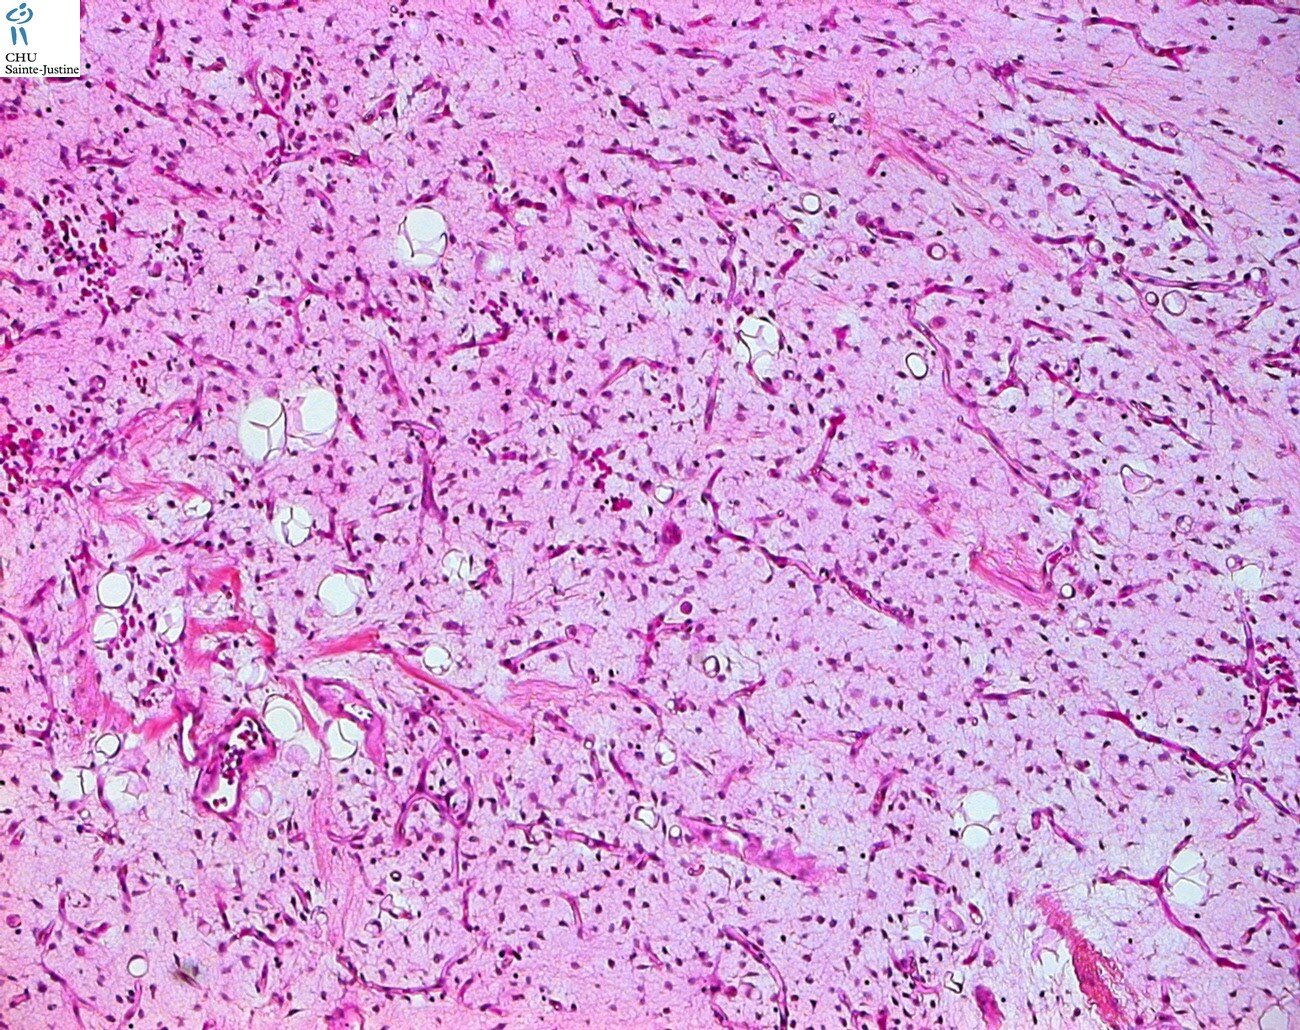

benign adypocytic tumors

| lipoma |

| lipoblastoma |

| lipoblastomatosis |

| well differenciated liposarcoma and atypical lipomatous tumor |

| dedifferentiated liposarcoma |

| myxoid/round cell liposarcoma |

| spindle cell liposarcoma |

| pleomorphic liposarcoma |

| mixed-type liposarcoma |

| liposarcoma |